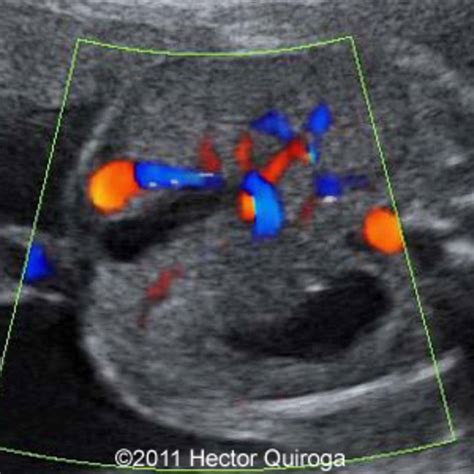

The identification of a Persistent Right Umbilical Vein is primarily achieved through high-resolution fetal ultrasonography. During the mid-trimester scan (typically between 18 and 22 weeks), sonographers examine the fetal abdomen to ensure that the umbilical vein is entering the liver correctly. When a PRUV is present, the sonographer will observe the following characteristic signs:

• The umbilical vein courses to the right side of the gallbladder, rather than the left.

• The vessel takes a slightly different anatomical path toward the portal system.

• The color Doppler ultrasound shows a change in the direction of the vascular flow compared to the expected norm.

Because these findings can be subtle, ultrasound technicians and maternal-fetal medicine specialists are trained to look for these specific markers when the abdominal anatomy does not appear completely symmetrical. Once identified, the radiologist or obstetrician will conduct a detailed survey of the entire fetus to rule out any associated structural abnormalities.